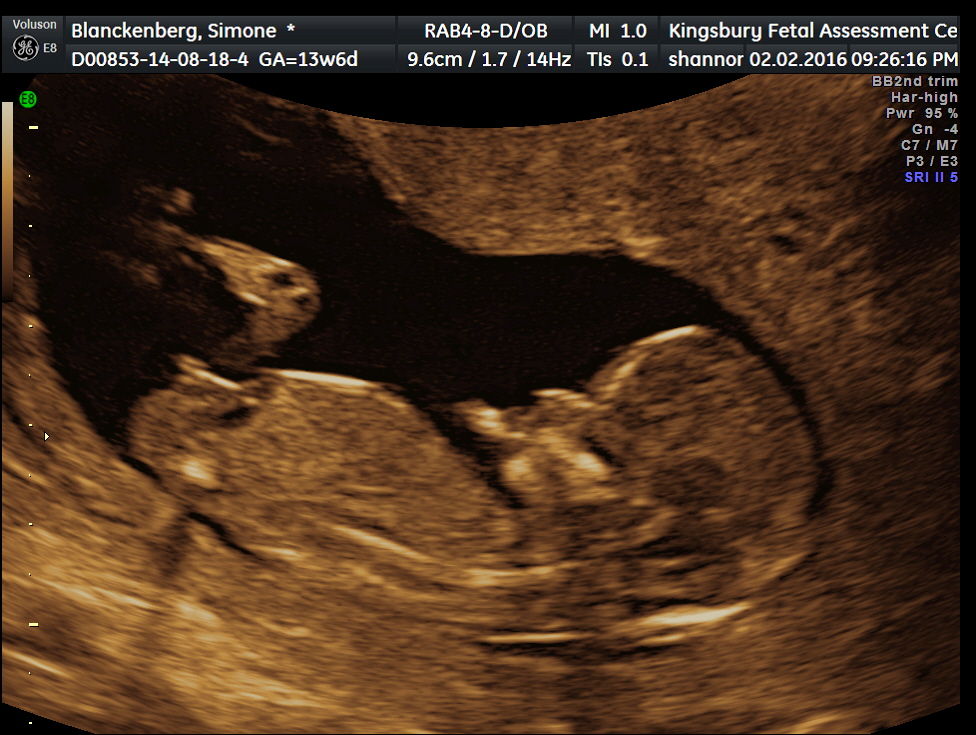

We are expecting a baby boy at the beginning of August. I am 13 weeks pregnant and so far everything looks good. We feel blessed on so many levels. The fact that I have fallen pregnant so easily at the first possible opportunity, the fact that I have a new life growing inside me, the fact that in among our heartache and pain we can find some joy in new life.